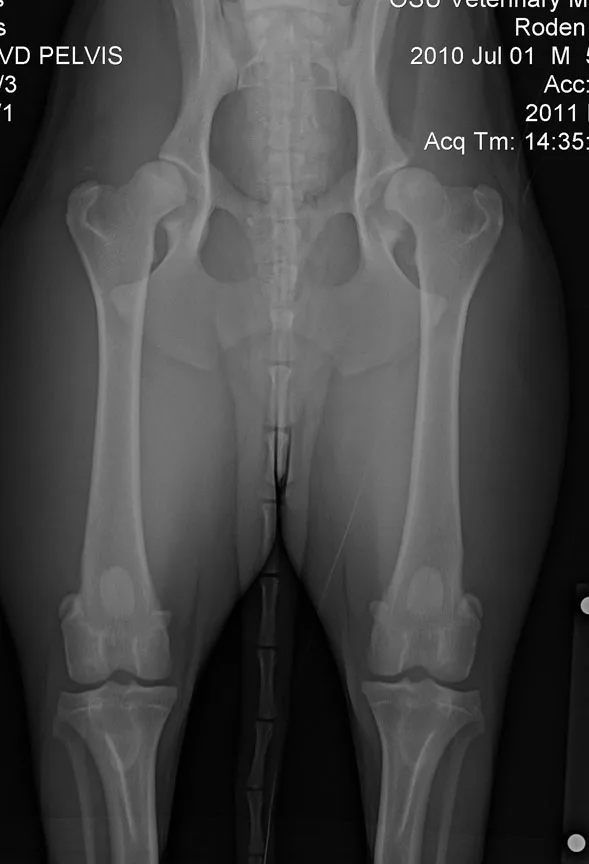

- Hip-extended ventrodorsal view to assess joint congruency (Figure 2); investigate Orthopedic Foundation for Animals (OFA) certification

(Left): Hip-extended ventrodorsal radiograph of a 10-month-old Australian shepherd with lameness and bunny-hopping gait at the run. Note the bilateral decreasedcoverage of the femoral heads by the acetabula and laxity present in the coxofemoral joints with increased severity in the left joint. (view larger image)